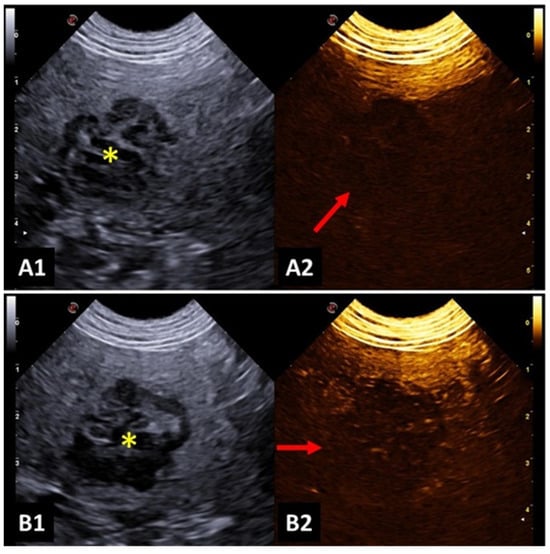

4. Applicability of CEUS

4.5. Spleen

4.7. Liver and Biliary System